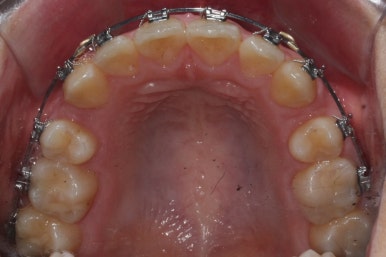

이제 가지런하게 하는 작업은 거의 종료되었고, 향후의 과정은 남은 이 뽑은 자리를 당겨주어 틈을 없애주면서도 입도 뒤로 좀 넣어주는 것이 되겠습니다.

위아래 아주 단단한 철사로 지탱해주면서 (앞니쪽에 고리가 달린 철사) 앞-뒤 치아를 서로 당겨주면서 이 뽑은 자리를 서서히 없애줍니다.

틈새를 모으는 작업을 반복적으로 행해주면 얼핏 봐서는 이뽑은 줄 모르게 치아가 서로 붙어있는 상황이 됩니다.

이제 이 뽑은 자리는 충분히 다 닫혔고, 틈새가 다시 벌어지지 않는지를 몇 개월에 걸쳐 확인한 뒤 그동안 디테일한 마무리 과정을 해주게 됩니다.